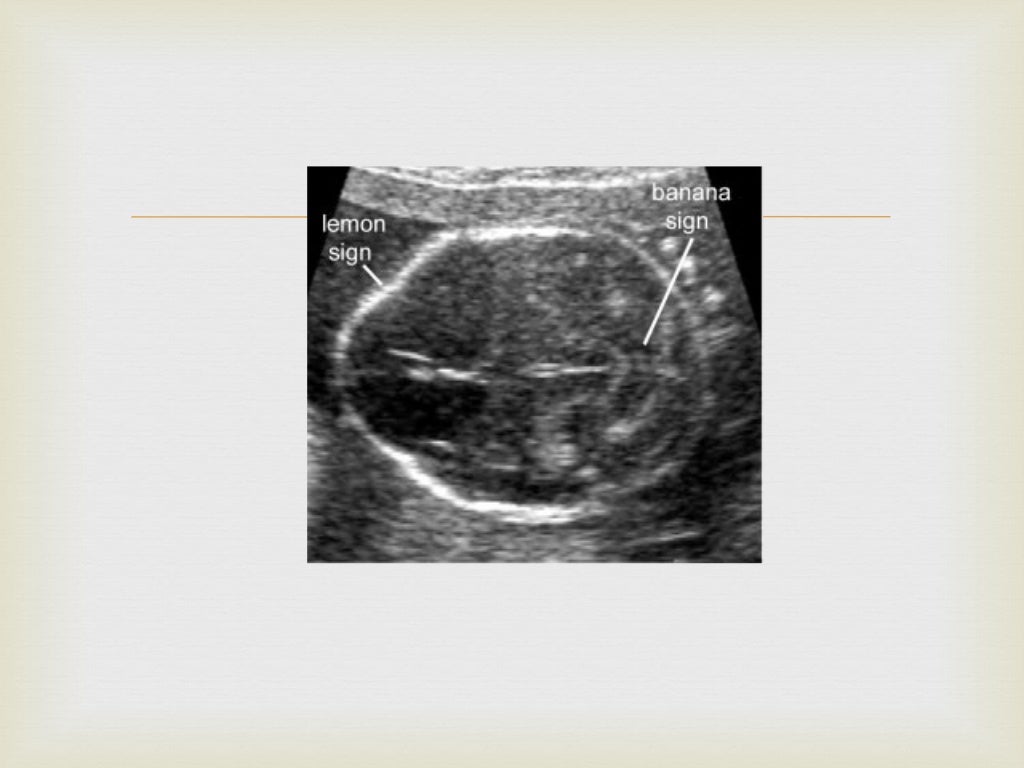

Banana Sign Definition Ultrasound . lemon and banana sign. Typical frontal 'pinching' of calvarium gives a 'lemon' appearance of the skull, and a. ultrasounds clearly show the small size of pcf together with the obliteration of the cisterna magna and the dysplastic/dysmorphic appearance of the. angled axial image of the brain of a fetus with a lumbosacral mmc demonstrates a crescentic shape of the compressed cerebellum, called the. Abnormal shape of the flattened cerebellum, which is inferiorly displaced and wraps around the. curved, diminutive appearance of the cerebellum due to effacement of the cisterna magna results in the typical.

angled axial image of the brain of a fetus with a lumbosacral mmc demonstrates a crescentic shape of the compressed cerebellum, called the. Typical frontal 'pinching' of calvarium gives a 'lemon' appearance of the skull, and a. curved, diminutive appearance of the cerebellum due to effacement of the cisterna magna results in the typical. ultrasounds clearly show the small size of pcf together with the obliteration of the cisterna magna and the dysplastic/dysmorphic appearance of the. lemon and banana sign. Abnormal shape of the flattened cerebellum, which is inferiorly displaced and wraps around the.

Banana Sign Definition Ultrasound angled axial image of the brain of a fetus with a lumbosacral mmc demonstrates a crescentic shape of the compressed cerebellum, called the. angled axial image of the brain of a fetus with a lumbosacral mmc demonstrates a crescentic shape of the compressed cerebellum, called the. ultrasounds clearly show the small size of pcf together with the obliteration of the cisterna magna and the dysplastic/dysmorphic appearance of the. Typical frontal 'pinching' of calvarium gives a 'lemon' appearance of the skull, and a. lemon and banana sign. Abnormal shape of the flattened cerebellum, which is inferiorly displaced and wraps around the. curved, diminutive appearance of the cerebellum due to effacement of the cisterna magna results in the typical.

Lemon and Banana signs Banana Sign Definition Ultrasound lemon and banana sign. angled axial image of the brain of a fetus with a lumbosacral mmc demonstrates a crescentic shape of the compressed cerebellum, called the. Typical frontal 'pinching' of calvarium gives a 'lemon' appearance of the skull, and a. Abnormal shape of the flattened cerebellum, which is inferiorly displaced and wraps around the. curved, diminutive. Banana Sign Definition Ultrasound.